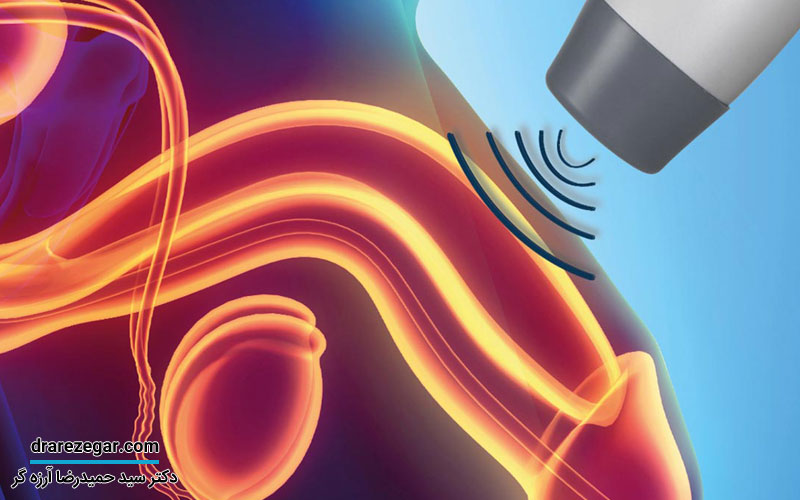

• برای انجام آزمایشات تصویربرداری و تهیه عکس های کامل از کلیه ها و دستگاه ادراری سونوگرافی یا سی تی اسکن انجام شود.